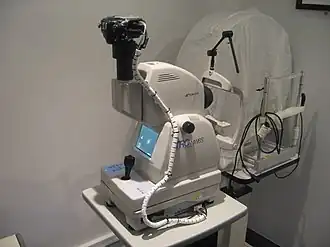

Specialized tests

Optical coherence tomography (OCT) is a medical technological platform used to assess ocular structures. The information is then used by eye doctors to assess staging of pathological processes and confirm clinical diagnoses. Subsequent OCT scans are used to assess the efficacy of managing diabetic retinopathy, age-related macular degeneration, and glaucoma